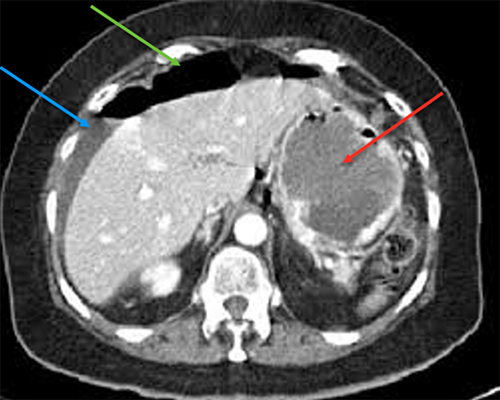

Le diagnostic est tout à fait possible, à évoquer ici en première intention devant l’âge (> 40 ans) et la symptomatologie (douleurs fébriles en fosse iliaque gauche et hypogastre).

– de la localisation de la douleur en fosse iliaque gauche ;

– du syndrome inflammatoire : fièvre à 38,5 °C avec hyperleucocytose à la biologie ;

– de l’argument de fréquence de cette pathologie à cet âge (la prévalence des diverticules sigmoïdiens est de plus en plus importante avec l’âge, après 40 ans).